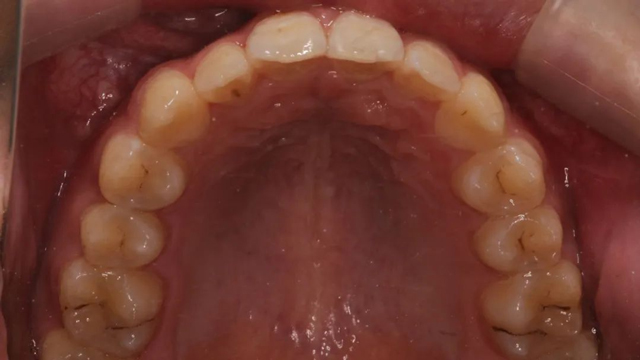

2021年8月(矯正前口內照)

這位小患者的口腔問題包括:牙列不齊,個別門牙反頜,左上尖牙完全埋伏阻生,另外,CBCT顯示右上門牙牙根腭側內還有一顆多生牙。

談到具體的治療方案,王亞楠醫生表示,整體的治療步驟是先拔除多生牙,一周后拆線,拆線當天拔除滯留乳牙,并對埋伏阻生尖牙行開窗術,通過粘貼牽引扣進行牽引,一周后開始佩戴隱形牙套。